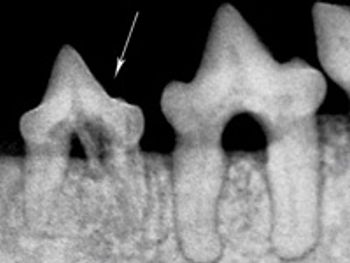

Was this dog's tooth root abscess the cause of its severe, progressive systemic illness?

Sorting through your choices for repairing these deep-seated defects.